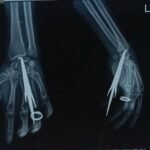

सुकमा में घरेलू विवाद के दौरान एक व्यक्ति अपने ही पुत्र द्वारा किए गए हमले में गंभीर रूप से घायल हो गया था। घटना में पीड़ित की जांघ में एक तीर धंस गया था, जबकि दूसरा तीर कलाई के पास घुसकर हाथ की महत्वपूर्ण नस (नर्व) को दबा रहा था। स्थिति अत्यंत संवेदनशील थी। समय रहते उपचार न मिलने की स्थिति में हाथ की स्थायी क्षति हो सकती थी और पीड़ित की जान को भी खतरा हो सकता था। घायल को तत्काल जगदलपुर डिमरापाल चिकित्सालय लाया गया, जहां रात्रि लगभग 2 बजे आर्थोपेडिक्स विभाग की टीम ने तत्परता से उपचार प्रारंभ किया। सहायक प्राध्यापक, आर्थोपेडिक्स विभाग डॉ. आदित्य कौशिक ने विभागाध्यक्ष डॉ. सुनीत पाल के मार्गदर्शन में जटिल शल्य प्रक्रिया को सफलतापूर्वक अंजाम दिया। चिकित्सकीय जांच में पाया गया कि यद्यपि रोगी हेमोडायनामिक रूप से अस्थिर नहीं था, फिर भी कलाई में धंसा तीर नस पर दबाव बना रहा था, जिससे स्थायी नर्व डैमेज का गंभीर खतरा उत्पन्न हो गया था। टीम द्वारा अत्यंत सावधानी और विशेषज्ञता के साथ दोनों तीरों को सुरक्षित रूप से निकाला गया। विशेष रूप से कलाई क्षेत्र में की गई सटीक प्रक्रिया के माध्यम से हाथ की नस को होने वाली संभावित क्षति को समय रहते रोक लिया गया। इस जटिल हस्तक्षेप में एनेस्थीसिया विशेषज्ञ डॉ. गुलाब सिंह काशी ने कुशलता से उपयुक्त क्षेत्रीय एनेस्थीसिया प्रदान किया, जिससे पूरी प्रक्रिया सुरक्षित और सुचारु रूप से सम्पन्न हो सकी। चिकित्सकों के अनुसार, ऐसी चोटें अत्यंत घातक सिद्ध हो सकती हैं, विशेषकर जब वे नसों के समीप हों। मध्य रात्रि में त्वरित निर्णय, अनुभवी चिकित्सकीय हाथों और समन्वित टीमवर्क के कारण यह जीवन-रक्षक उपचार संभव हो पाया। वर्तमान में रोगी की स्थिति स्थिर है और हाथ की कार्यक्षमता सुरक्षित रहने की उम्मीद जताई गई है। डॉक्टरों के टीम वर्क, अस्पताल अधीक्षक डॉ. अनुरूप साहू के कुशल नेतृत्व, समय पर चिकित्सकीय हस्तक्षेप के महत्व को और हॉस्पीटल में उपलब्ध विशेषज्ञ सेवाओं और चिकित्सकों की प्रतिबद्धता का प्रमाण प्रस्तुत करती है। डिमरापाल मेडिकल कॉलेज के अधीक्षक डॉ. अनुरूप साहू के कुशल निर्देशन में डाक्टरों की टीम बेहतर व्यवस्था के साथ मरीजों की देखरेख में जुटी है। हॉस्पीटल में साय सरकार के सुशासन की झलक साफ नजर आने लगी है।